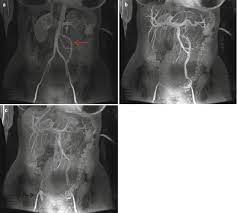

Figure 1 From Gonadal Vein Embolization Treatment Of Varicocele And Pelvic Congestion Syndrome Semantic Scholar